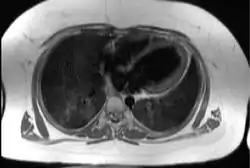

![]() Трансаксіальне ехокардіографічне зображення серця, що ілюструє типовий ступінь підшкірної і епікардіальної жирової тканини (показаний білим кольором) у пацієнта з синдромом Алстрема Трансаксіальне ехокардіографічне зображення серця, що ілюструє типовий ступінь підшкірної і епікардіальної жирової тканини (показаний білим кольором) у пацієнта з синдромом Алстрема | |